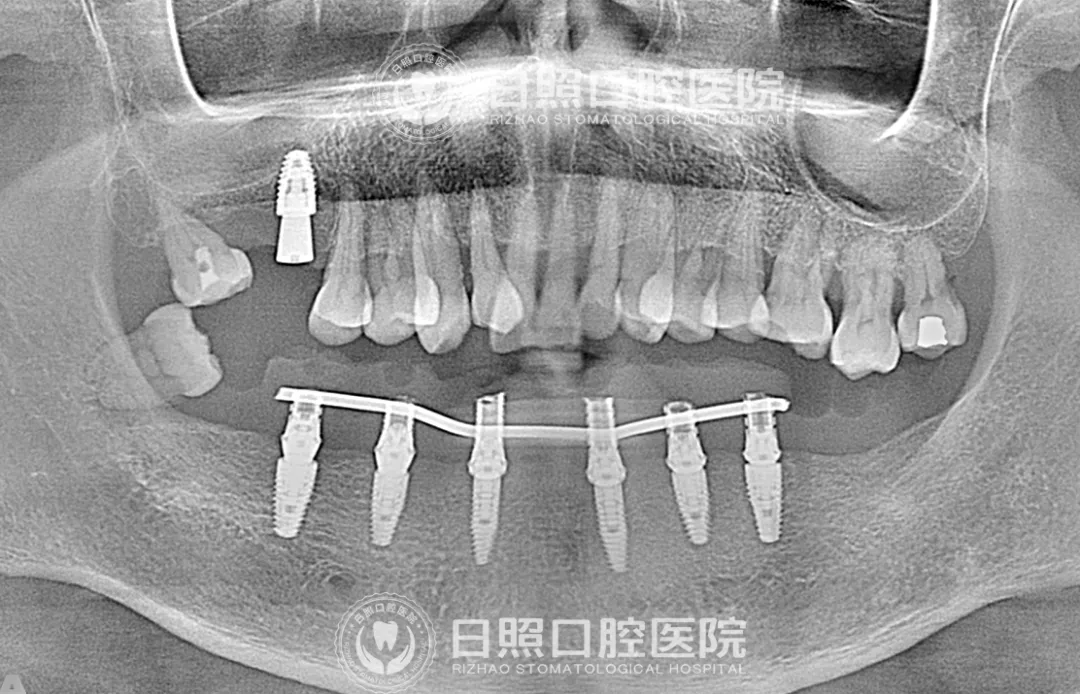

术前,刘大叔下颌仅剩5颗牙齿

术后,下颌植入6颗种植体

王新全主任提前一周为刘大叔设计了种植方案,将他的口腔影像数据通过软件进行三维重建,根据其下颌骨拟种植区骨量条件规划设计种植体路径,手术当日,拔除了刘大叔下颌松动的4颗牙齿,随后,王新全带领种植团队将6颗种植体逐一植入,实现6个位点的精准种植,手术过程约2个小时,种植完成后当日,即为刘大叔试戴、固定预设计制作的即刻义齿。